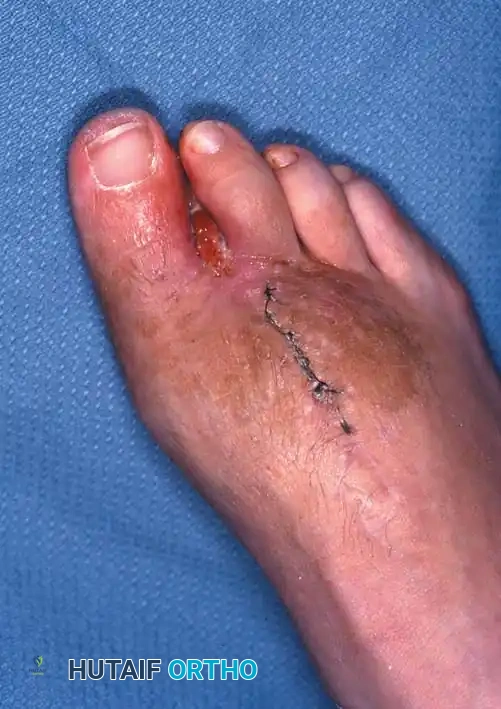

Clinical photo fifth toes A

Clinical photo fifth toes B

3. Fifth Toe Incision: Fashion a lateral flap long enough to cover the lateral bony defect, closing the wound by approximating the flap to the medial web skin.